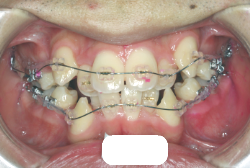

叢生(そうせい)

凸凹な歯並びのことを叢生といいます。矯正歯科に来院する患者様の主訴の中で、最も多いのが「配列の凸凹を真っ直ぐにしたい」というものです。歯の大きさと顎の大きさの調和がとれていないことが原因です。

凸凹を主体としたケースの場合、当院の平均治療期間は18ヶ月ですので、このケースは少し長めに経過しました。理由の一つは凸凹の程度がかなり重症だったと言うことですが、もう一つは、右下第2大臼歯が45度くらい前傾していたため、それを整直化させるために時間を要したと考えています。いずれにしても最終結果は大変よい状態と思います。

治療前は並びが乱れて見た目が悪いというのはもちろん問題ですが、歯科医学的に一番困るのは噛み合わせが悪いという点です。上下の犬歯(3番目の歯)は、上下的に離れた位置にあるため接触することができません。つまり歯としては存在していても、歯としては機能していないということです。